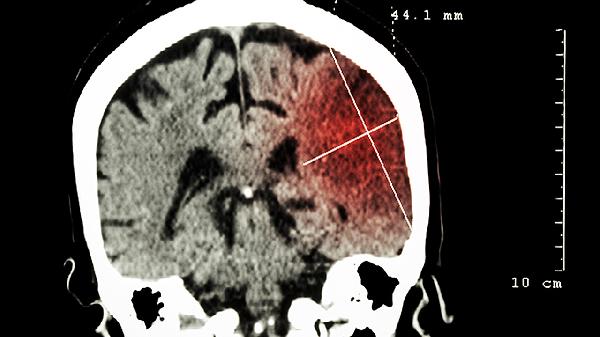

川芎、丹参等活血成分能扩张脑血管,增加血氧供应,缓解因颈椎病、动脉硬化等引起的头晕、头痛症状。合并高血压患者需监测血压变化,避免与抗凝药物联用。